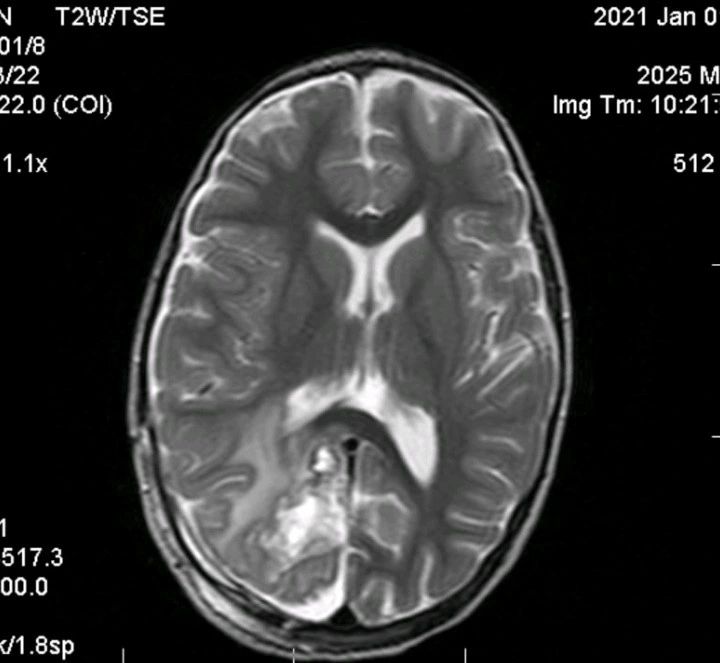

- 影像学检查: 脑部 MRI 显示明显的颅内占位伴水肿(见附图),高度怀疑为脑肿瘤。

🔪 【诊断陷阱与外科困境】 由于影像学表现极像肿瘤,且缺乏全身性或感染性体征,患儿接受了神经外科切除手术。 然而,术后病理结果却出人意料:中枢神经系统结核瘤(CNS tuberculoma)!